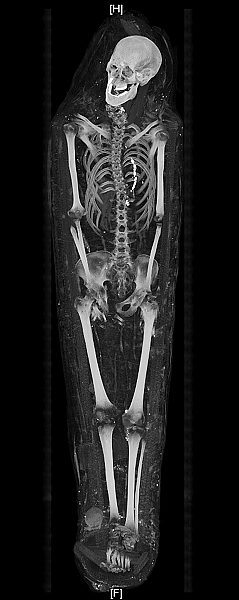

Mumie eines Erwachsenen in geometrischer Umwicklung mit

dachartigem Kopfbau

Röntgenaufnahme

Byzantinische Zeit, spätes 4. - 7. Jh. n. Chr.

Koptischer Friedhof bei Karara

Innen: Organisches Material, Palmfaserschnüre, Palmblattmittelrippen,

diverses Pflanzenmaterial, Textilien

Außen: Leinentuch, Bänder aus naturbelassenem und gefärbtem

Leinen (0,5 – 0,8 cm breit); Leder (Sandalen), winzige Metallreste

L. 185,5 cm, max. Br. 43,5 cm (Kopfbereich), H. 17 cm (Körpermitte)